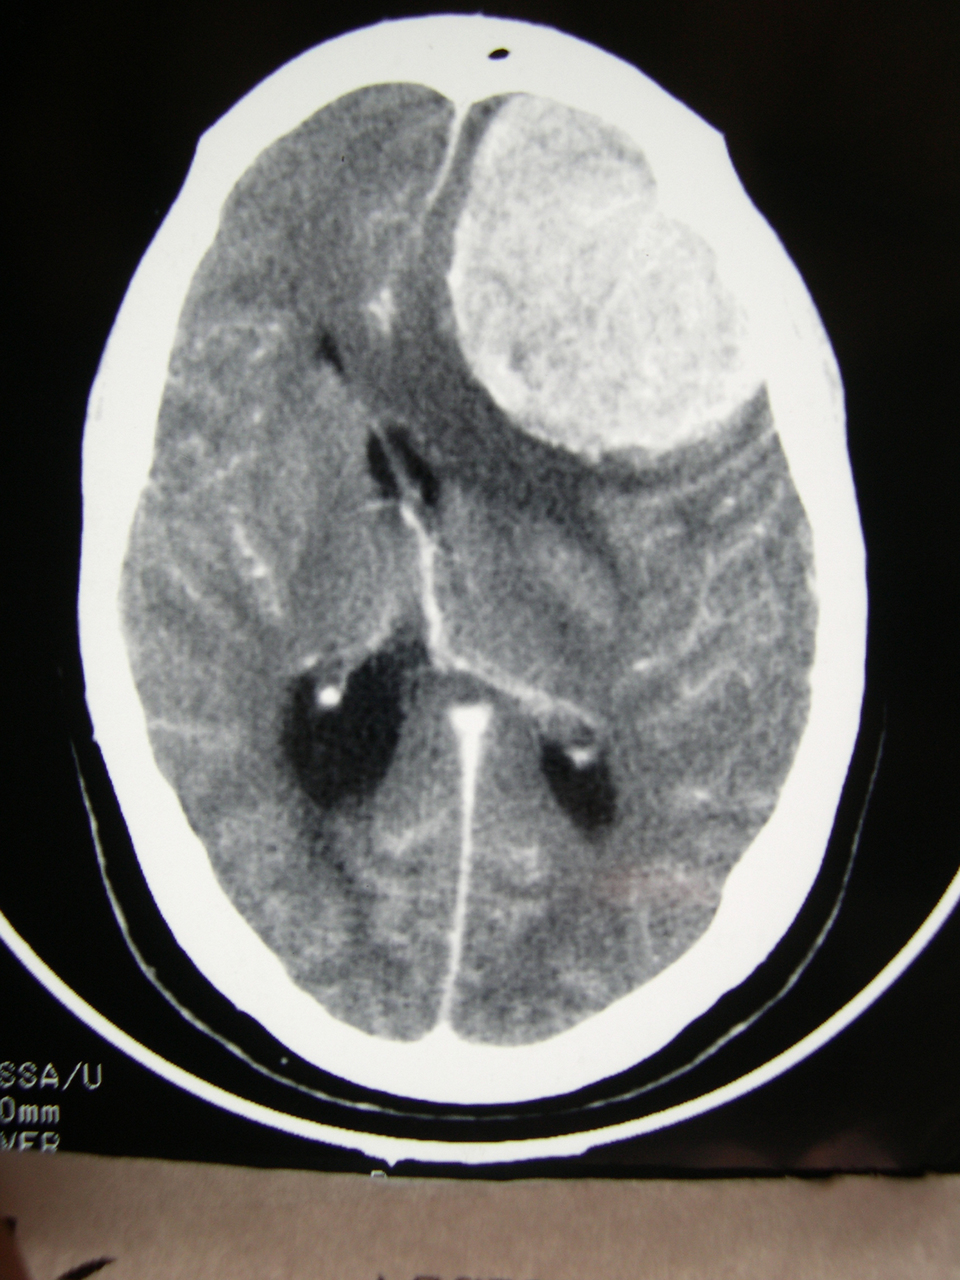

Quel est votre diagnostic ? Méningiome Angioglioblastome Sarcoïdose Pachyméningite Sclérose tubéreuse de Bourneville OK Valider mes réponses